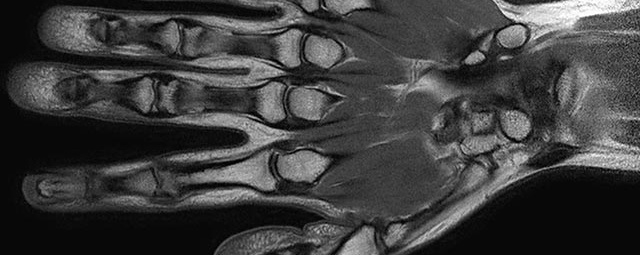

- Beurteilung von Knochen, Bändern und anderen Weichteilstrukturen der Gelenke nach Unfall.

- Ausbreitungsdiagnostik bei Gelenkentzündung, z.B. im Rahmen von rheumatischen Grunderkrankungen